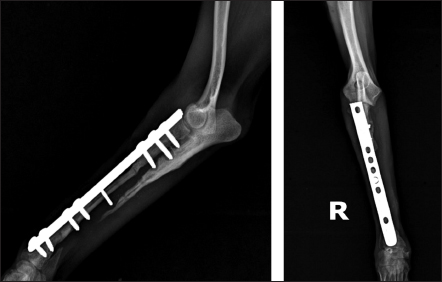

Fig. 3. Mediolateral radiograph of antebrachial bones after the revision surgery. Left: the ulna of the healthy thoracic limb after harvesting of the cortical autograft. Right: fixation of the cortical autograft with dynamic compression plate.

То harvest the autogenous cortical graft, a caudal approach to the contralateral ulnar diaphysis was used (Fig. 2). The subcutaneous tissue was bluntly dissected, and thereafter retraction was maintained using Gelpi retractors. A Hohmann retractor was placed between the ulna and radius to prevent iatrogenic damage to the radius. A 4.8 cm long bone segment of the ulnar diaphysis was removed by means of an oscillating saw. The ostectomy and periosteum were removed en bloc and transferred into the surgical gap of the right radius. At both ends of the cortical autograft, a cancellous graft soaked with 1,000 IU recombinant human erythropoietin (Binocrit®, 2000 IU, Sandoz GmbH, Kundl, Austria) was applied for optimization of osteoinduction and angiogenesis. To collect the cancellous graft, a small incision was made over the craniolateral aspect of the greater trochanter. A 3.5-mm hole in the proximal humeral metaphysis was created with a drill bit and a bone curette was used to harvest the cancellous graft. Then, it was inserted into the recipient site as soon as possible to minimize cell death. After proper alignment of bone fragments, they were fixed with a dynamic compression plate (1.5 mm thickness) and 8 cortical screws: 2 in the distal radial fragment, 3 in the cortical graft, and 3 in the proximal radial fragment (Fig. 3). The intradermal layer was closed with an absorbable monofilament suture material (PDX, 3-0, VetSuture, France), followed by non-absorbable skin sutures (Nylon, 3-0, Kruuse, Denmark).